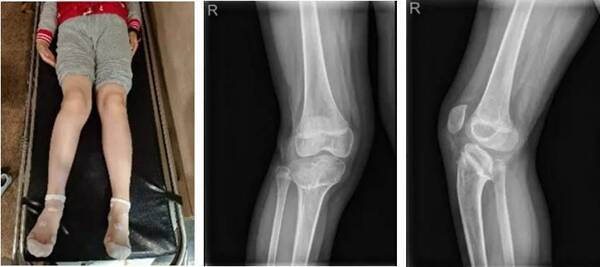

△小李妹妹的腿部狀況;X線片

在丁煥文教授的安排下小李妹妹進(jìn)行X線片、CT、MR等傳統(tǒng)影像檢查,患兒X線片和CT掃描二維斷面圖像均發(fā)現(xiàn)患者右膝有嚴(yán)重后傾畸形改變。于是,拿到CT數(shù)據(jù)的樹蟻智能數(shù)字精準(zhǔn)外科云服務(wù)系統(tǒng)團(tuán)隊(duì)使用建模軟件對(duì)患者的全下肢進(jìn)行了精準(zhǔn)分離式三維重建,對(duì)小李妹妹重建后的患處進(jìn)行了解剖方位對(duì)齊和多方位的精準(zhǔn)三維測量,發(fā)現(xiàn)小李妹妹因?yàn)楣趋客鈧投嗄曛w畸形原因,右下肢短縮明顯,達(dá)41mm

△臨床診斷:右膝部畸形

1.    矢狀面畸形:脛骨平臺(tái)后傾26.4736°

2.    額狀面畸形:內(nèi)翻6°

3.    右下肢短縮畸形(41mm